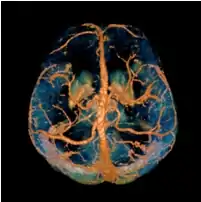

A volume rendered brain QSM acquired at 3 Tesla and reconstructed with morphology enabled dipole inversion (MEDI).

Quantitative susceptibility mapping (QSM) provides a novel contrast mechanism in magnetic resonance imaging (MRI) different from traditional susceptibility weighted imaging.[1][2][3][4][5] The voxel intensity in QSM is linearly proportional to the underlying tissue apparent magnetic susceptibility, which is useful for chemical identification and quantification of specific biomarkers including iron, calcium, gadolinium, and super paramagnetic iron oxide (SPIO) nano-particles. QSM utilizes phase images, solves the magnetic field to susceptibility source inverse problem, and generates a three-dimensional susceptibility distribution. Due to its quantitative nature and sensitivity to certain kinds of material, potential QSM applications include standardized quantitative stratification of cerebral microbleeds and neurodegenerative disease, accurate gadolinium quantification in contrast enhanced MRI, and direct monitoring of targeted theranostic drug biodistribution in nanomedicine.